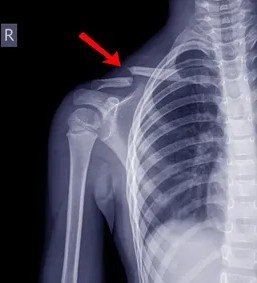

На   рентгеновском    снимке:  часть  грудной   клетки,  плечевой  пояс  и   рука.

И   перелом   КЛЮЧИЦЫ.

Снимок грудной клетки , с включением плечевых костей  и черепа . Как будто со спины снят . Перелом есть . Трещины ребер . Перелом ключицы .

Части тела: 10 Жез 3 Пент 2 Мечей - Акцент идет на спину - позвоночник, верно,   там   видно  его!  но так как этого варианта нет,  смотря на изображение карт мысли как будто бы рентген локтевого сустава - получается рука.   рука  есть  на   снимке

мне упрямо видится голова и грудная клетка. верно))Но как это может быть разом на одном снимке в реальности не представляю. Но все таки там череп на рентгене

перелом  есть .ага))   есть) но   перелом   ключицы.  Череп - лобная доля.

Снимок грудной клетки , с включением плечевых костей  и черепа . Как будто со спины снят . Перелом есть . Трещины ребер . Перелом ключицы .  Браво!! Вы   МОЛОДЕЦ!)